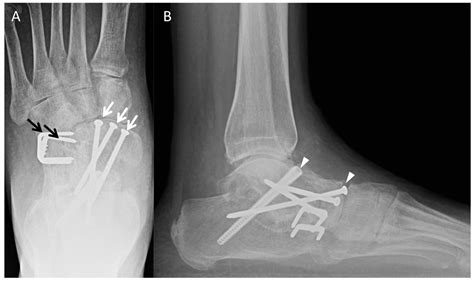

• Bone Grafting: In some cases, bone grafts may be used to promote healing and fusion. These grafts can be taken from the patient's own body or from a donor.

• Fixation: The bones are aligned and held in place using screws, plates, or rods. These fixation devices provide stability while the bones heal and fuse together.